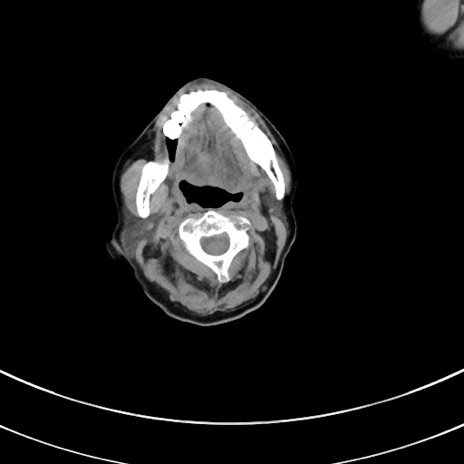

冠状断像

【症例】70歳代 女性

【主訴】心窩部痛

【現病歴】延髄病変の精査・加療にて神経内科入院中。本日より心窩部痛あり。

【既往歴】虫垂炎

【身体所見】右下腹部を中心に圧痛と反跳痛あり。

【データ】WBC 10900、CRP 0.02